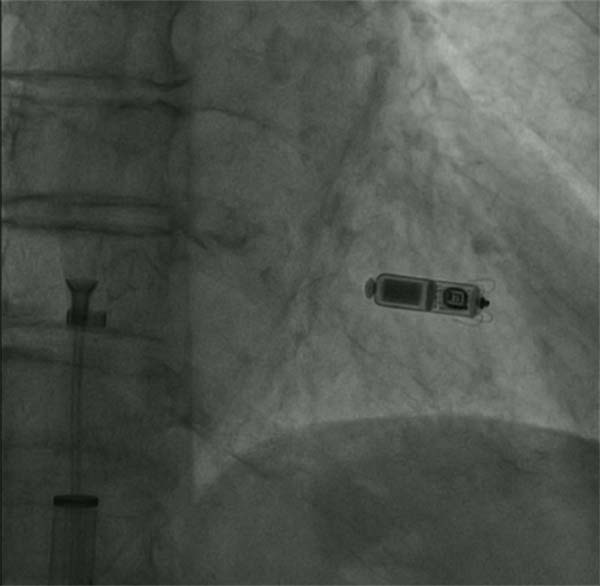

11月15日,心血管内科在导管室为患者实施无导线起搏器治疗,手术取得圆满成功,手术过程顺利,患者术后窦性心律平稳,起搏器起搏感知功能良好。心血管内科凭借精湛的医术和丰富的临床经验,成功挽救了高龄老人的生命,为进一步接受其他治疗打下了良好的基础。

据了解,无导线起搏器俗称胶囊起搏器,就像一粒胶囊药物大小,体积较传统起搏器减少93%,是世界上最小的起搏器,目前我们使用的型号重量只有1.7g,寿命可达13-15年。主要特点是体积小,抗核磁,可以接受1.5T和3.0T全身核磁检查,同时植入方便快捷,经股静脉途径就能完成,术后恢复更快,两天就可恢复日常工作和生活。此例无导线起博器手术的成功实施,标志着应急总医院心血管内科的救治技术迈上了新台阶、实现了新跨越。

起搏器释放后